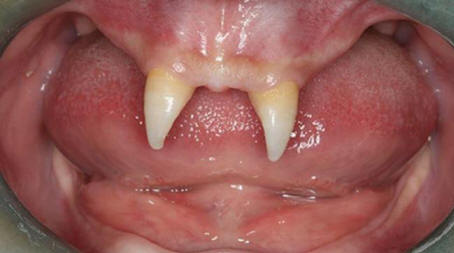

7. Dítě se narodilo s 28 zuby

V roce 2010 matka mnoha dětí Marta Matoniová šokovala obyvatele Okres Nyanaruhua v Keni, který porodí zdravého chlapce s 28 zuby. Podle Petera Mumera, místního klinického úředníka, Mart porodila svého syna Jamese Mwangiho přímo doma.

Ale poté, co byla objevena úžasná odchylka, matka a dítě bylo převezeno do místního zdravotnického zařízení. Teď Mwangi je již čtyři roky, roste bez jakýchkoli komplikací a v roce Ve věku 8 měsíců už snědl giteri (tradiční keňské jídlo) kuchyně).